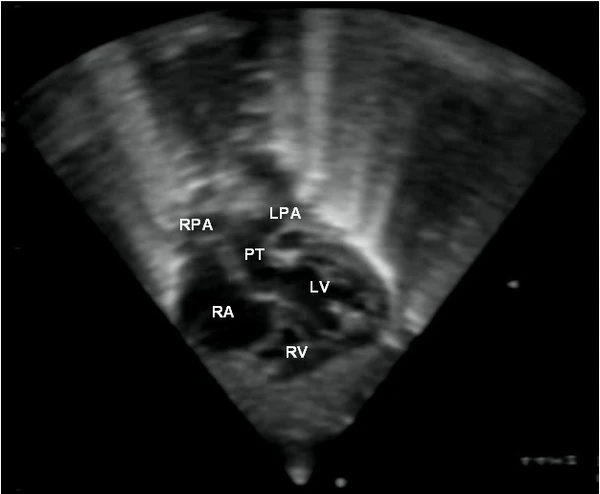

Полную транспозицию в период беременности обнаружить сложно. На УЗИ сердце будет выглядеть нормальным, четырёхкамерным, от него будут отходить два сосуда. Диагностическим критерием порока в данном случае может стать параллельный ход главных артерий, в норме перекрещивающихся, а также визуализация крупного сосуда, который берёт начало в левом желудочке и делится на 2 ветви — лёгочные артерии.